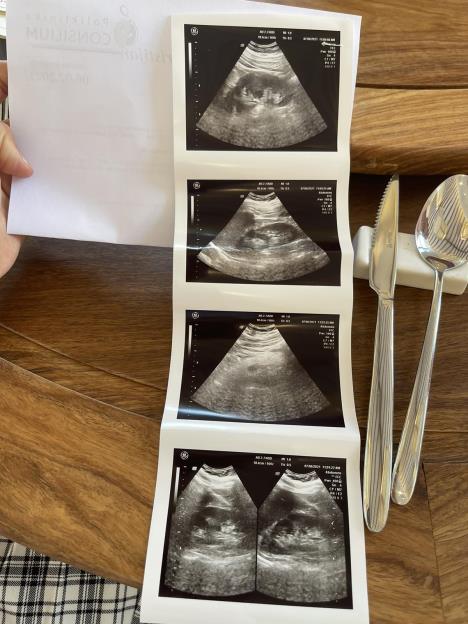

Inače, ekipa Kurira ekskluzivno je došla do snimka Kristijanovog bubrega, koji je radio u jednoj privatnoj klinici u Novom Sadu, gde je i izvadio krv i testirao se na razne bolesti. Tim lekara moraće da proceni da li su kompatibilni i da da svoje stručno mišljenje.

img3ee72b17a6aa756fe9d8d52bf0045ac2v.jpg

Foto: Kurir Privatna Arhiva